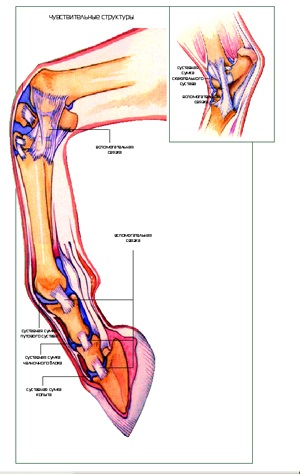

Elemek - az egyik egyedülálló és legfontosabb biológiai megoldás, amely nélkülözhetetlen a mozgás. Ők is elég rugalmas, hogy lágy mozdulatokkal, és ugyanabban az időben, egy meglehetősen szilárd hogy ellenálljon a tömeg, a test és mozgatni. A lábak a lovak és más emlősök egyik legfontosabb szerepeket játszott szervek, amelyek kötődnek a csontok, az ízületek. Ezek tartalmazzák az összes erejét és rugalmasságát. Ez a szövet típusát körülveszi a közös mindkét oldalán és a hívott ínszalagok (ínszalagok vagy kisegítő).

Csomagok nem nagyon jól rajzolt ló, de elég erős. Ezek erősített poluizgibom (180 fok) között azok kezdete és vége. Ez a kialakítás lehetővé teszi, hogy mindig, minden helyzetben, bármilyen szögben, hogy elég feszült. Támogatása nélkül az ilyen szerkezetek a szervezetben, az ízületek hamarosan elromlott, nem tudta elviselni a nehéz súly. Ő forog és nem állapítottak meg, amelynek eredményeként a halálát. Amikor a ló gyors járás, a vezetékek futnak szögben, és ez megköveteli a sok erőt. Ha a szalagok nem elég erős, ez vezethet a nyújtás vagy könnyezés, valamint a kárt a csukló és a lábak.

Under vezetékek és közöttük a csontot a csont terjed a kapszula Az ízületi folyadékban. Hasonló, hogy a zsák támogatja a szinoviális membrán és szinoviális folyadék megakadályozza a szivárgást. A kapszula rugalmas és mivel ez teszi ki is esik egy jelentős terhelést. Azt is meg lehet sérült túlterhelés miatt. Gyakran nyúlik az ízületi tok, ritka esetekben, a bűnös ínszalagok és korlátozza, amely alatt fekszik a csont.

Gyulladás patahenger általában fejlődik a következőképpen. Először az érintett ízületi tok, elválasztó ín és a csont. Ebben a szakaszban, a betegség még nem lehet kimutatni a röntgen. Ezután, a gyulladás rögzíti a befedő porc a csont és a környező inak. Ennek eredményeként, hibák fordulnak elő, és lazítása ínszalagok és porcszövet. Ha a gyulladás tovább terjed, ez is hatással van a csont, és vezet a fibrotikus degeneráció az ín. Előrehaladott stádiumban növekedések között felmerülő ín és a csont. Ez megváltoztatja a szerkezetét a csont és a csont bomlani kezd.